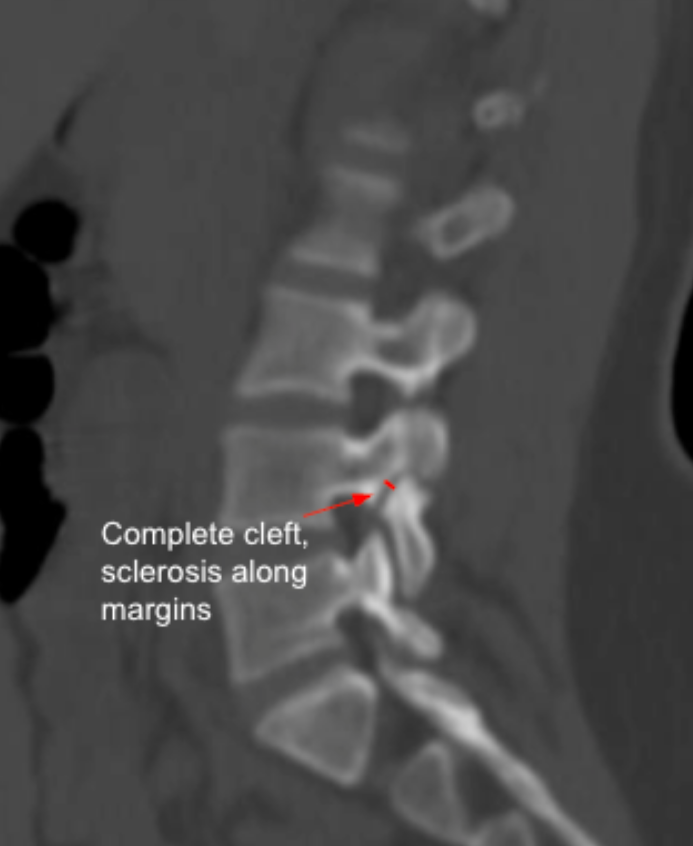

Assessment of the pars interarticularis evaluates for spondylolysis, stress reactions, or chronic non-union, which are common in young athletes, degenerative spondylolisthesis, and in association with lumbosacral transitional vertebrae (Bertolotti’s syndrome). Key features include:

These features distinguish acute stress fractures from chronic pars defects.

• Chronic Pars Defect: Complete cleft

• Chronic Pars Defect: ≥ 2-3 mm

• Chronic Pars Defect: Prominent marginal sclerosis

Defect width > 3 mm with sclerosis strongly indicates chronic non-union.